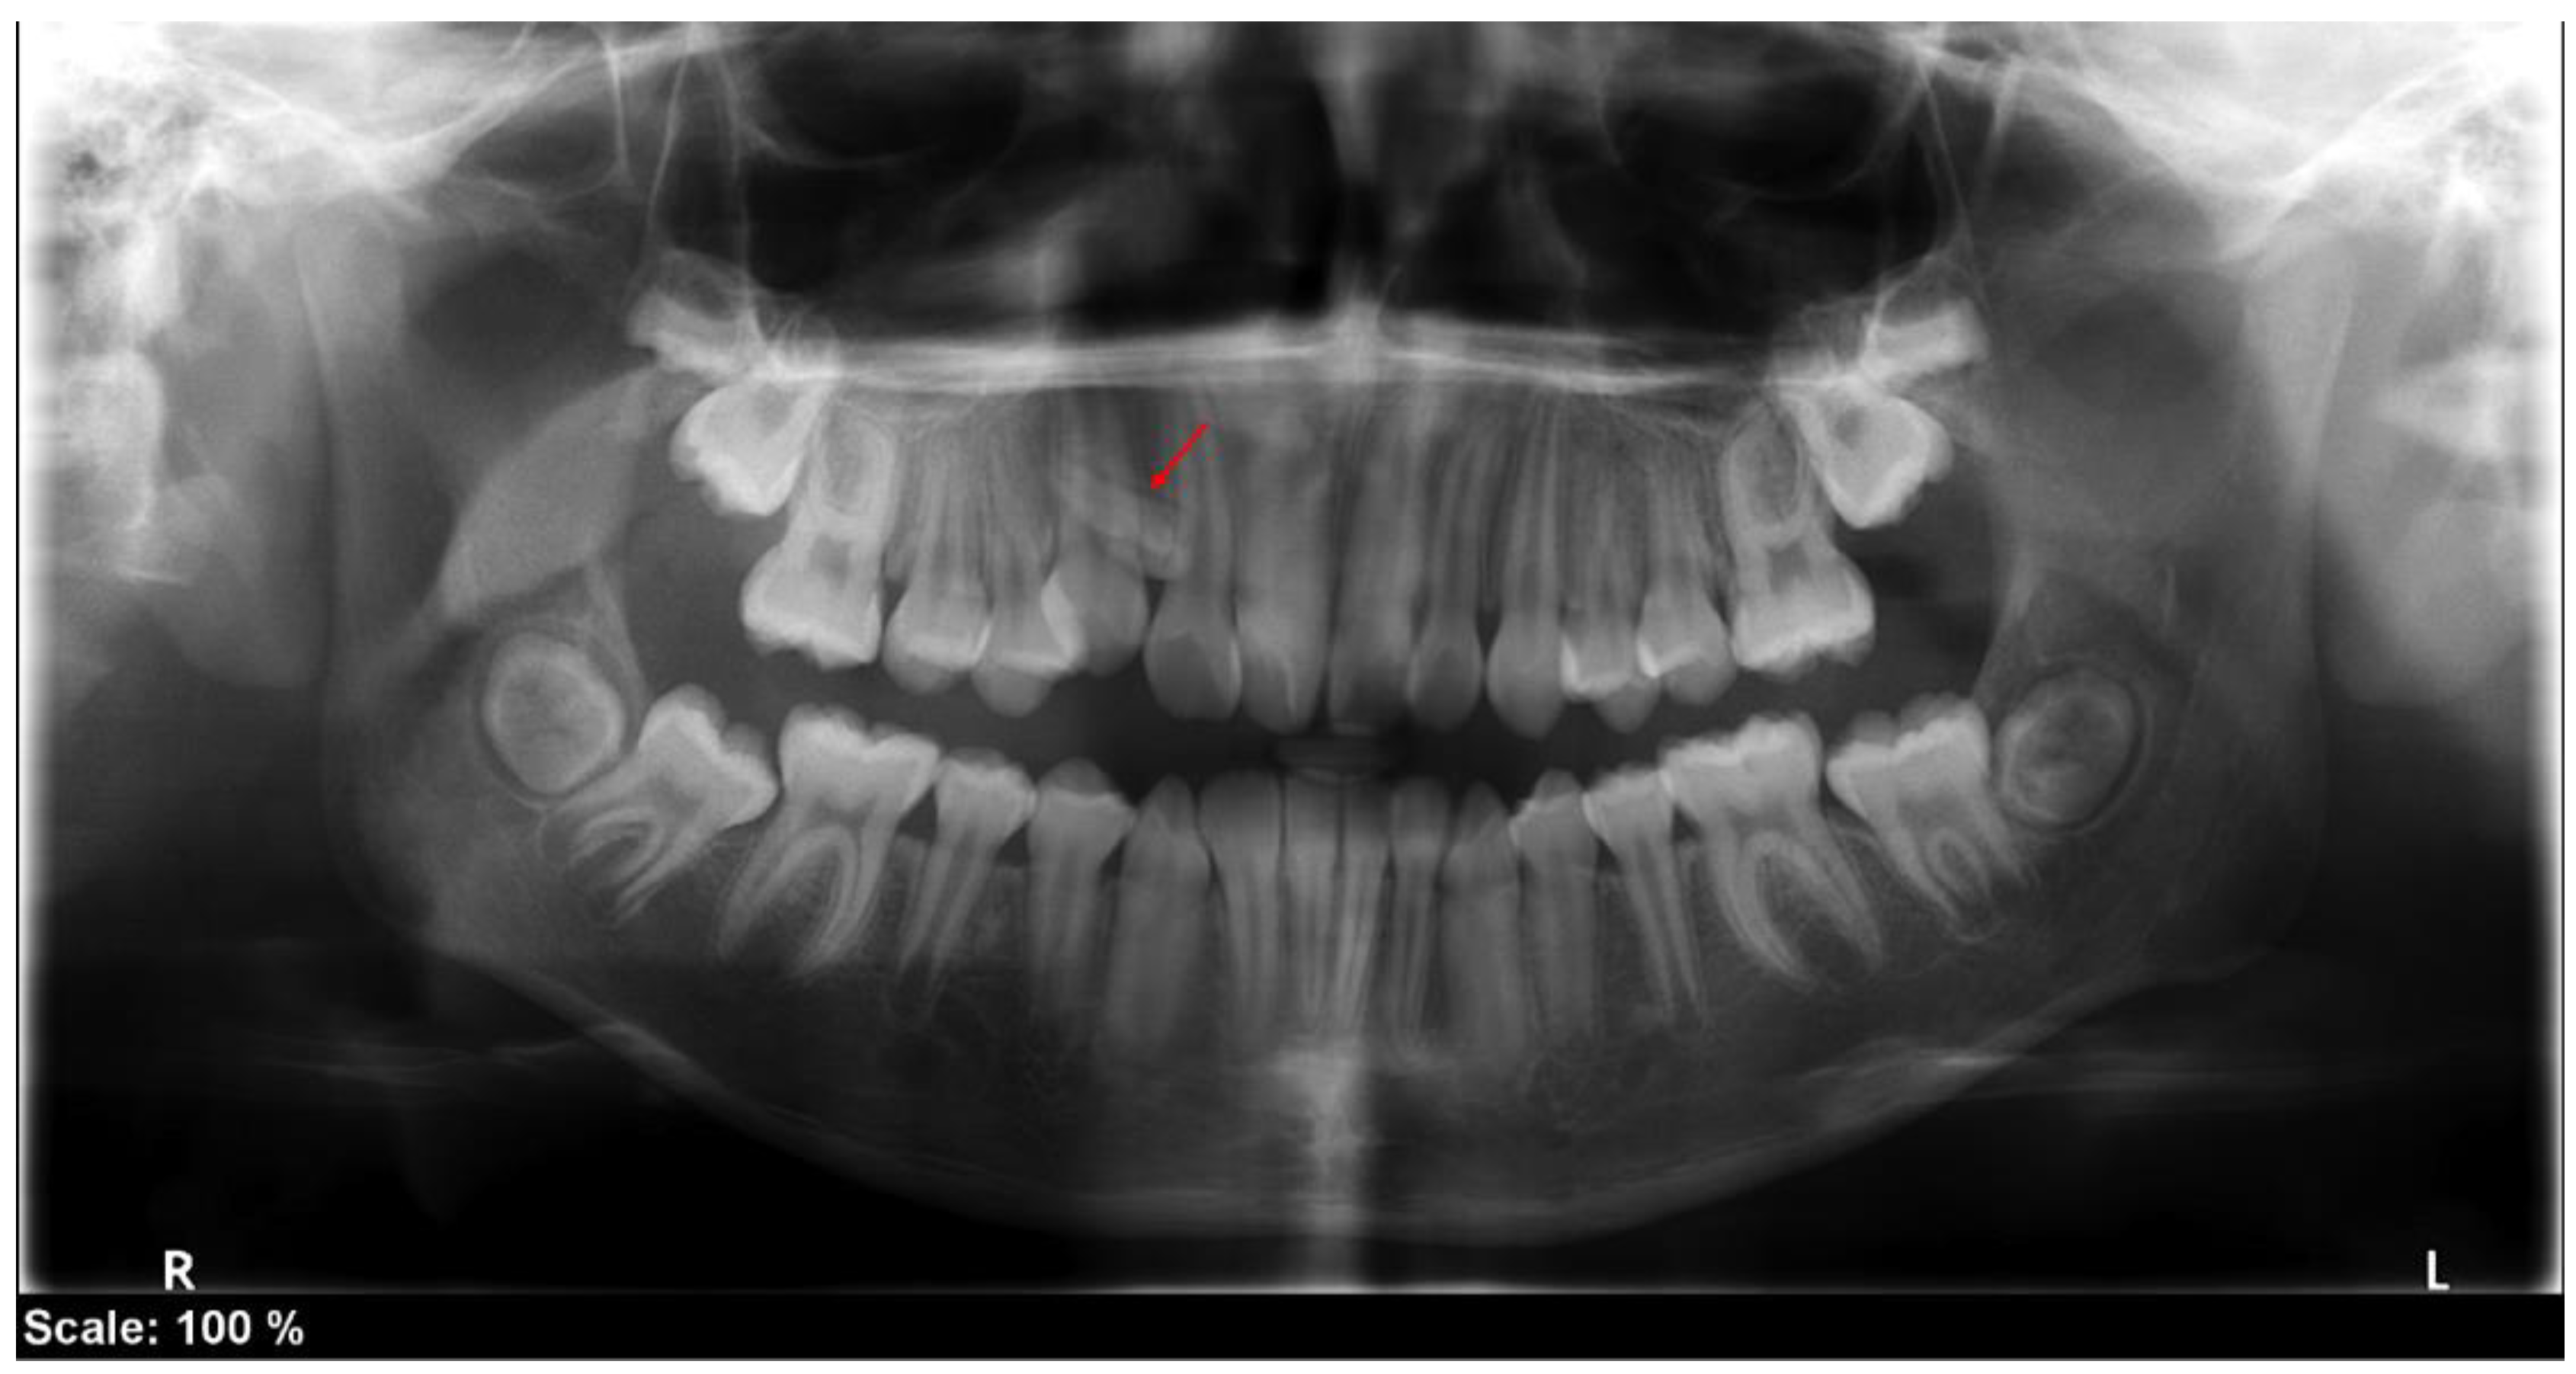

2. Case Report